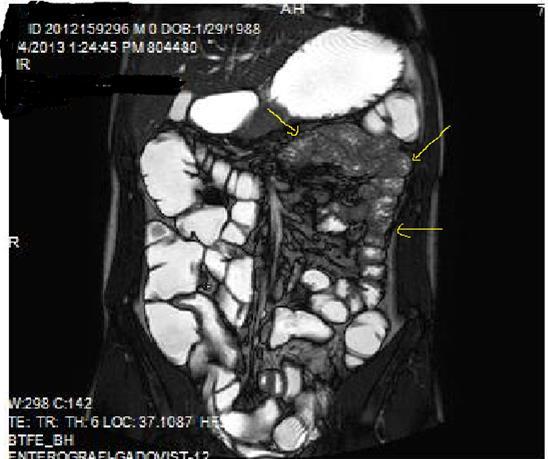

Diffusion-weighted imaging(DWI) and magnetization transfer imaging(MTI) are the new imaging sequences and techniques that can be performed for the accurate diagnosis of Crohn’s disease2, 9, 10. In case of active inflammation, restricted diffusion on high-b-value is conducted at DWI in case of Crohn’s disease, whereas infrequent for ulcerative colitis. To my experience, DWI may play a collaborating role in the imaging of patients who can’t tolerate OCA’s or in patients in whom IV contrast agent use is contraindicated5, 9.MTI may reflect the enteric fibrosis and stricture development in Crohn’s disease via transfer of energy from the free water protons inside the lumen, to the macromolecules especially for the collagen fibers at the bowel wall9, 10, 11, 12. Motility of the small intestine can be visualized by cine MRI via fast T2W images or true fast steady-state precession imaging, abnormal bowel motility and inflammatory activity in Crohn’s disease can be shown, based on wall thickness, ulceration and T2 signal intensity 9, 11, 12, 13 (Figure 1a-b).

Figure 1a.Diffuse mucosal involvement and increased wall thickness with loss of valvula conniventes in the ileal segments on T2W coronal images after OCA administration, seen on 30 years old female with moderate Crohn’s disease.

Figure 1b.Diffuse bowel wall enhancement in the small intestine due to Crohn’s disease on the Post-contrast T1W coronal sequence.